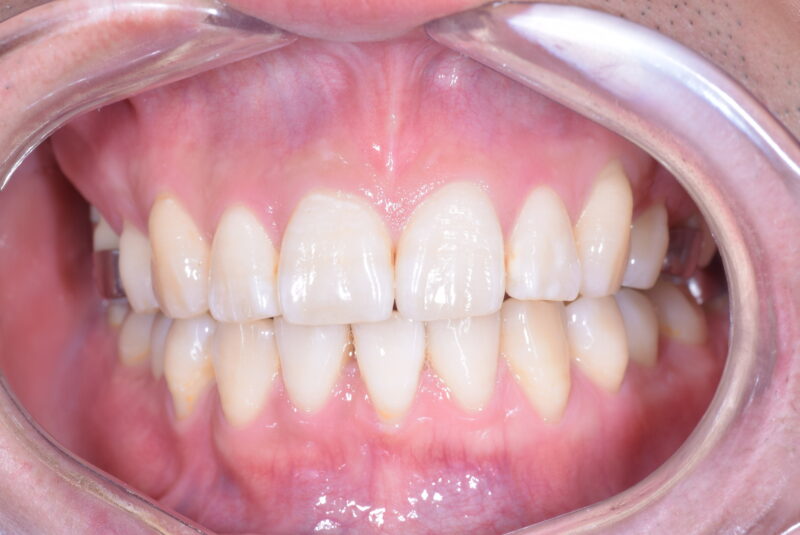

症例27 重度叢生症例

・治療前

・治療中

・治療後

①主訴 歯ならびが悪い

②診断名 前歯部叢生 Angle Cl. I

③年齢 20代女性

④治療に用いた主な装置 上顎:表側の装置 下顎:表側の装置

⑤抜歯部位 上顎:左右第一小臼歯 下顎:左右第一小臼歯

⑥治療期間 1年5か月

⑦治療費 850,000円

⑧リスク副作用 痛み・治療後の後戻り・歯根吸収・歯髄壊死・歯肉退縮などが一般的なリスクと副作用です。